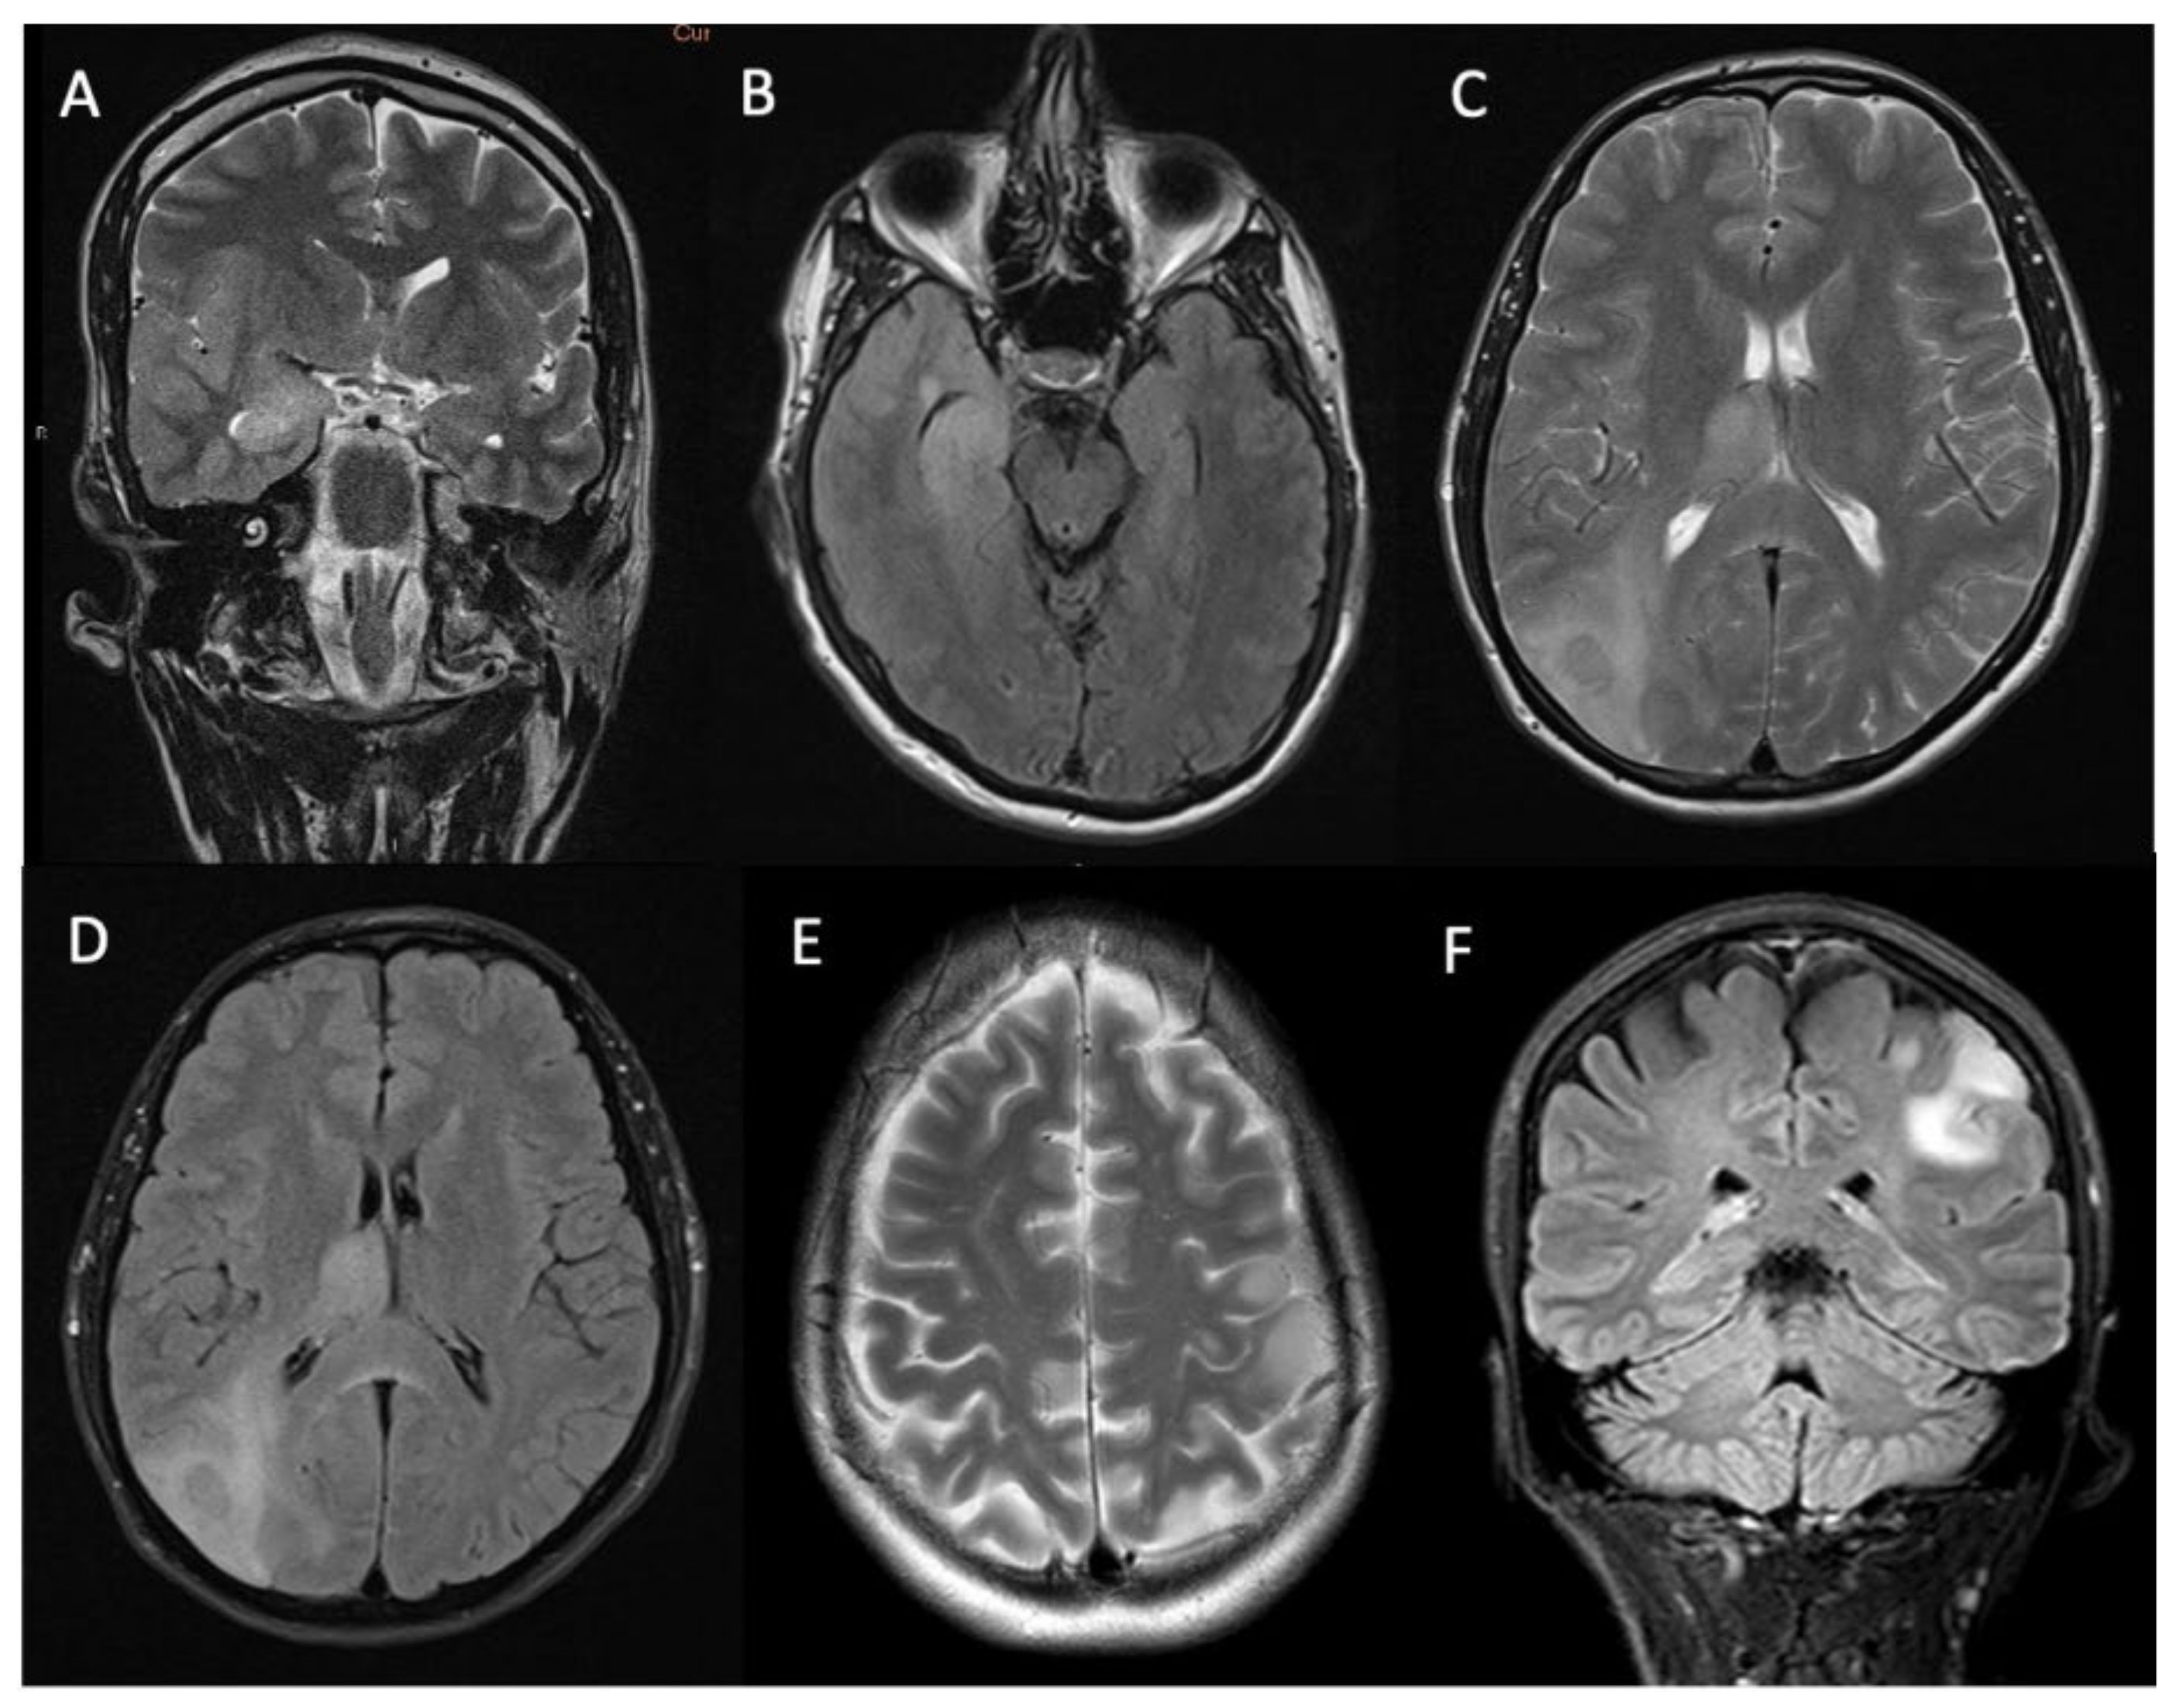

| Contrast enhancement | |

| Solid pattern | 18 (33%) |

| Rim enhancement | 17 (31%) |

| Non-enhancing | 19 (36%) |

| Contrast enhancement on diagnostic MRI (present vs. absent) | 15.2 (12.1 to 18.3) vs. 28.8 (21.3 to 36.2) months | p = 0.003 |

| Pattern of gadolinium enhancement (solid/patchy versus rim-enhancing with central necrosis) | 15.9 (12.5 to 19.3) vs. 14 (11.7 to 16.2) months | p = 0.57 |